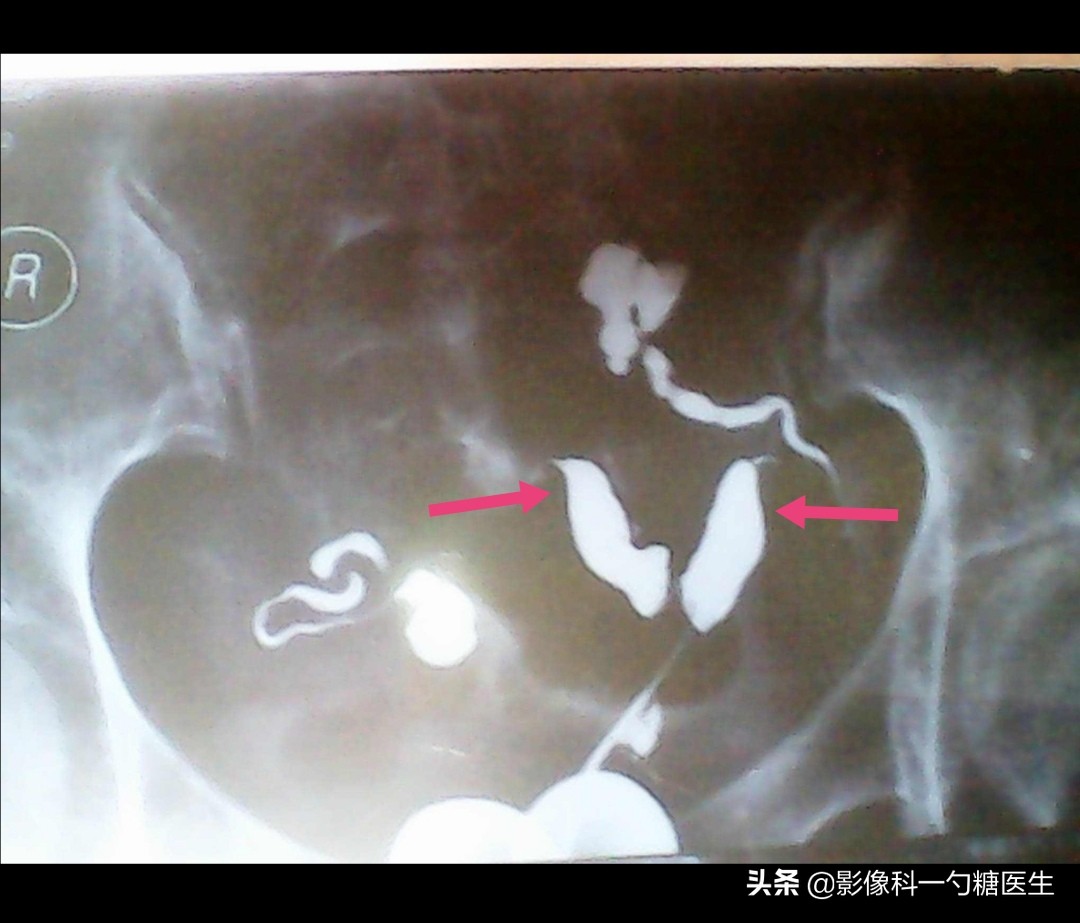

小余是上周来检查的病人之一,但只有她一个的检查结果是异常的,因为只剩一侧输卵管了(下图④)。

图④:小余的造影图

异位妊娠 即“宫外孕”,受精卵在子宫腔以外的部位着床、发育。最常见的部分为输卵管。

而只剩一侧输卵管的患者,怀孕几率本身就只剩50%了,如果对侧的输卵管堵塞不通,那自然受孕的几率几乎为零。

而切除了左侧输卵管的小余,右侧的输卵管虽然通畅,却也有少量积水,所以一直再难受孕。